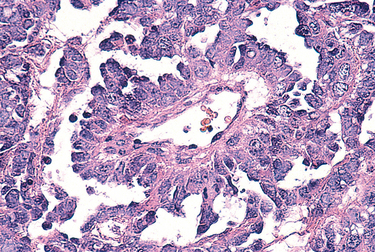

Morphology. The characteristic serous tumor may present on gross examination as either a cystic lesion in which the papillary epithelium is contained within a few fibrous walled cysts (intracystic) (Fig. 22-37A), or projecting from the ovarian surface. Benign tumors typically present with a smooth glistening cyst wall with no epithelial thickening or with small papillary projections. Borderline tumors contain an increased number of papillary projections (Fig. 22-37A and C). Bilaterality is common, occurring in 20% of benign serous cystadenomas, 30% of serous borderline tumors, and approximately 66% of serous carcinomas. A significant proportion of both serous borderline tumors and malignant serous tumors involve (or originate from) the surface of the ovary (Fig. 22-37C). On histologic examination, the cysts are lined by columnar epithelium, which has abundant cilia in benign tumors (Fig. 22-38A). Microscopic papillae may be found. Serous borderline tumors exhibit increased complexity of the stromal papillae, stratification of the epithelium and mild nuclear atypia, but destructive infiltrative growth into the stroma is not seen (Fig. 22-38B).75 This epithelial proliferation often grows in a delicate, papillary pattern referred to as “micropapillary carcinoma” and is thought to be the precursor to low-grade serous carcinoma (Fig. 22-38C). Larger amounts of solid or papillary tumor mass, irregularity in the tumor mass, and fixation or nodularity of the capsule are important indicators of probable malignancy (see Fig. 22-37B). These features are characteristic of high-grade serous carcinoma, which microscopically exhibits even more complex growth patterns and infiltration or frank effacement of the underlying stroma (Fig. 22-38D). The individual tumor cells in the high-grade carcinomas display marked nuclear atypia, including pleomorphism, atypical mitotic figures, and multinucleation. The cells may even become so undifferentiated that serous features are no longer recognizable. Concentric calcifications (psammoma bodies) characterize serous tumors, but are not specific for neoplasia. Ovarian serous tumors, both low- and high-grade, have a propensity to spread to the peritoneal surfaces and omentum and are commonly associated with the presence of ascites. As with other tumors, the extent of the spread outside the ovary determines the stage of the disease.

image

FIGURE 22-38 Serous cystadenomas. A, Papillary serous cystadenoma revealing stromal papillae with a columnar epithelium. B, Borderline serous tumor showing increased architectural complexity and epithelial cell stratification. C, Complex micropapillary growth defines a low-grade “micropapillary” serous carcinoma. D, Papillary serous cystadenocarcinoma of the ovary with invasion of underlying stroma.